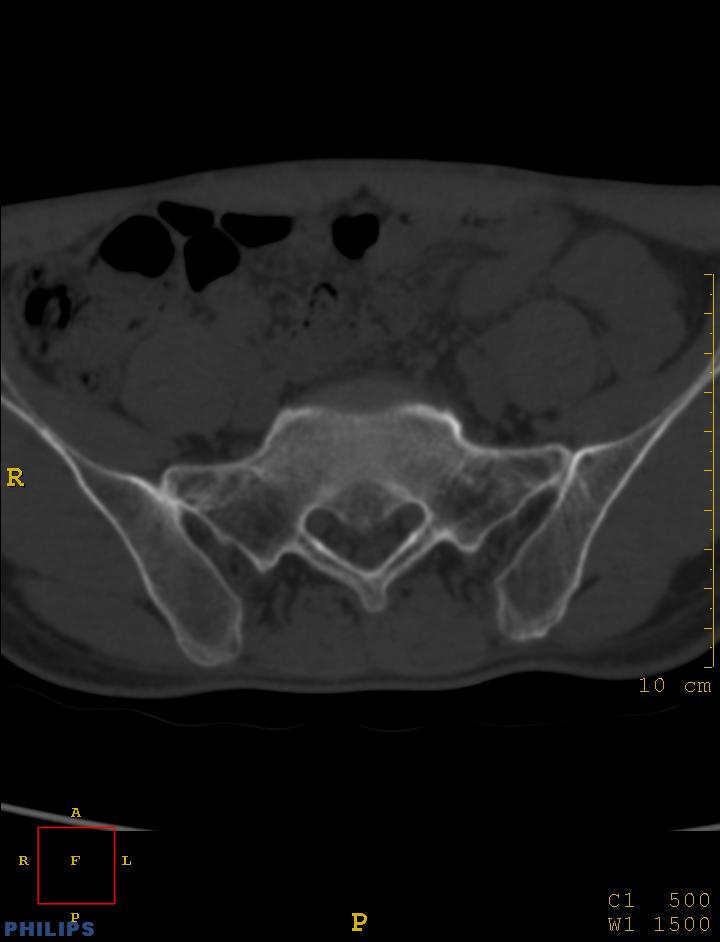

标题: CT14032:M34Y,双侧骶髂关节

m,34岁,腰痛三年,腰椎活动度明显减低,x片示腰椎竹节样改变

双侧骶髂关节面融合;强直脊柱炎

双侧骶髂关节骨性融合,软骨下囊性变,结合脊柱竹节样改变,典型的强直性脊柱炎。